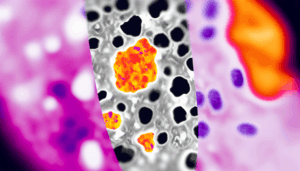

โรคด่างขาว หรือ ด่างขาว เป็นโรครูปแบบหนึ่งที่เกิดจากการเสื่อมของเซลล์ที่สร้างเมลานิน ซึ่งเป็นสารที่ทำให้สีผิวเกิดขึ้น อาการที่สังเกตได้คือการเกิดจุดขาวที่ผิวหนัง ซึ่งสามารถเกิดขึ้นได้ทุกส่วนของร่างกาย เมื่อเซลล์เมลานินถูกทำลายหรือเสื่อมสภาพ ทำให้ผิวหนังมีการขาดสีตามธรรมชาติ อาจเกิดขึ้นในบางส่วนเฉพาะ หรือกระจายไปในหลายๆ จุด โดยไม่กำหนดอายุหรือเพศในการเกิดโรคนี้

ถึงแม้ว่าสาเหตุที่แน่ชัดของโรคด่างขาวจะยังไม่เป็นที่ทราบ แต่มีหลายปัจจัยที่อาจเกี่ยวข้องกับการเกิดโรคนี้ หนึ่งในนั้นคือปฏิกิริยาของระบบภูมิคุ้มกันของร่างกาย ซึ่งอาจทำให้เซลล์ที่ผลิตเมลานินถูกทำลายลงได้ นอกจากนี้ ปัจจัยทางพันธุกรรมก็มีบทบาทในการเกิดโรคนี้ เพราะผู้ที่มีประวัติครอบครัวเป็นโรคด่างขาวมีโอกาสที่จะเป็นโรคนี้มากขึ้น ความเครียดก็เป็นหนึ่งในปัจจัยที่อาจนำไปสู่การเกิดโรคนี้ได้เช่นกัน โดยเฉพาะเมื่อเกิดเหตุการณ์เครียดในชีวิต ส่วนมากผู้ป่วยจะเริ่มมีอาการเพียงแค่จุดสีขาวเล็กๆ ก่อนที่จะแพร่ขยายออกไป